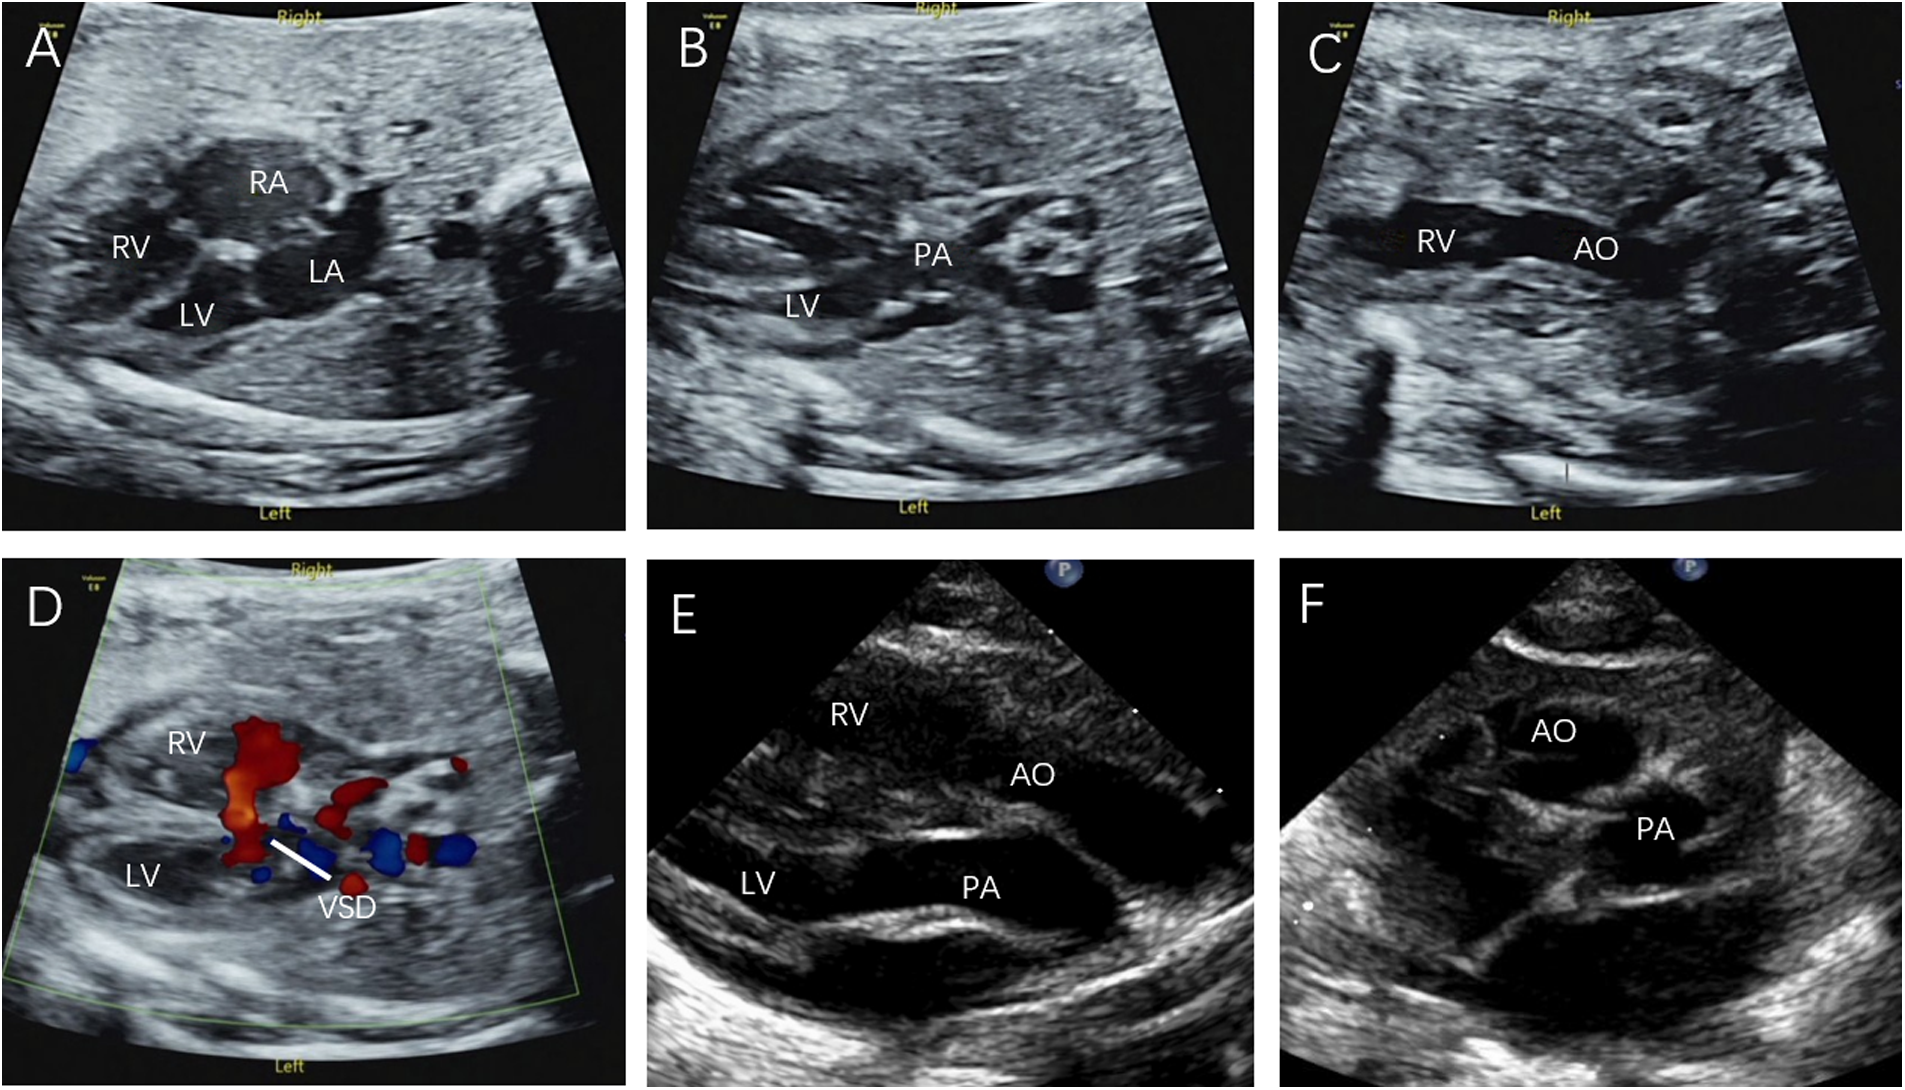

Figure 4

Fetal CC-TGA case confirmed by echocardiography at 23 weeks and 4 days. (A) Four-chamber heart view showing inconsistent atrioventricular connections, with the left atrium connected to the morphological right ventricle and the right atrium connected to the morphological left ventricle. (B–D) Right ventricular outflow tract view showing the pulmonary artery arising from the morphological left ventricle and left ventricular outflow tract view showing the aorta arising from the morphological right ventricle, with the aorta located anteriorly to the left of the pulmonary artery.

In the present study, 8 D-TGA patients were identified early in pregnancy. Six patients underwent induction of labour (Figures 1C,D), and two were induced in the second trimester. Additionally, 68 D-TGA patients were diagnosed in the second trimester. Of these, 62 underwent induction (Figures 2E,F), and six were observed until delivery. Fourteen patients with late-stage D-TGA were referred to our hospital. Six mothers underwent induction therapy, seven mothers continued their pregnancies at our hospital, and one delivered elsewhere (Figure 5). Fourteen patients experienced continued pregnancies and delivered full-term without preterm issues. Postnatal echocardiography confirmed D-TGA (Figure 6). Among the 9 children (10.0%) who underwent surgery, two passed away postoperatively. The remaining 7 patients achieved positive outcomes. Four children (5.2%) were discharged without surgery due to conditions such as pulmonary inflammation. One (1.3%) patient had no surgery and maintained a positive prognosis by telephone follow-up, as presented in Table 3.

Figure 6

Prenatal and postnatal diagnosis of D-TGA. (A–D) D-TGA with VSD at 24 w and 6 d gestation. (E) Parasternal long-axis view: The two great arteries are aligned in parallel, with the aorta located anteriorly on the right, originating from the right ventricle, and the pulmonary artery located posteriorly on the left, originating from the left ventricle. (F) The short axis view of the great arteries: The aorta and pulmonary artery are circumferential and adjacent rather than travelling normally (the longitudinal pulmonary artery surrounds the circular aorta).